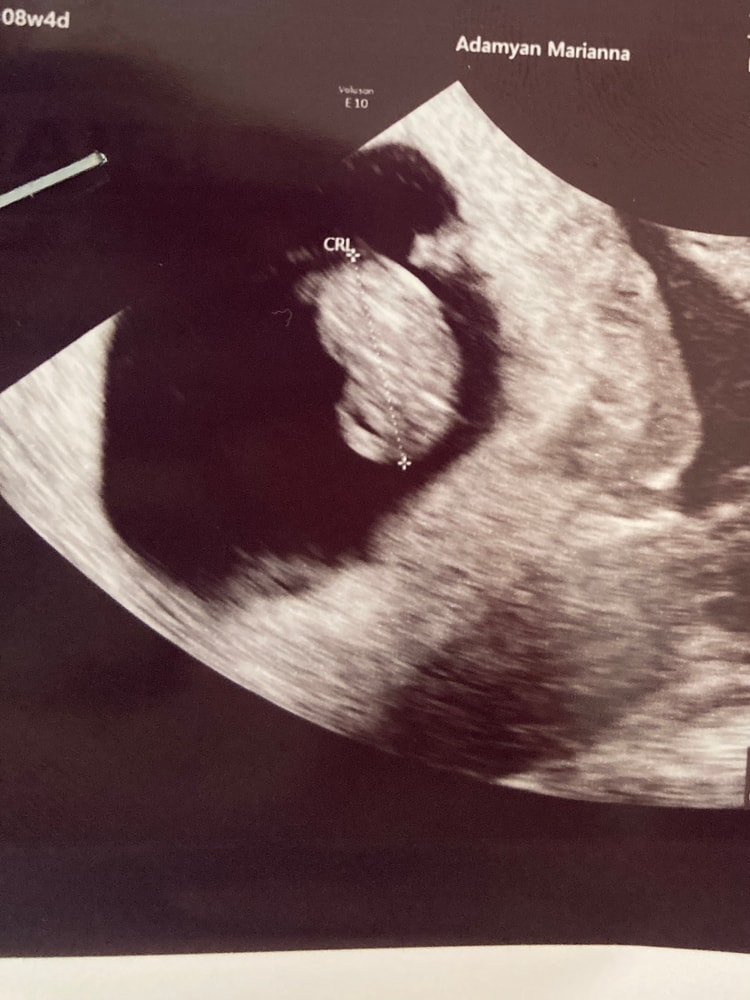

Девочки, привет, кто знающий и разбирается в снимках узи раннего срока, посмотрите пожалуйста, вообще ничего не понимаю 😅 Где голова, где что? 😂 Ручек, ножек вообще ещё не видно получается? Смотрела снимки других девочек на этом сроке, уже хоть как-то можно человека высмотреть, а у меня фасоль 🤦♀️ Это нормально, что он так выглядит?..( Врач смотрел пол минуты и ничего не объяснил, поэтому обращаюсь к Вам, всегда здесь подскажут и помогут ❤️

Срок по узи ставят 8 нед. Ктр 17,8 мм

Отправила вам в личку свой 3D снимок на точно таком же сроке 🤗 у вас правда просто со спины)

Да мне кажется, что это вид сзади) Ходила в 8.4, мне два снимка дали, один со спинки, тоже ничего не понятно, и один нормальный, там и голову и жопку видно, креветочка такая. Видимо просто узист не стал заморачиваться со снимками. Растите 🌸